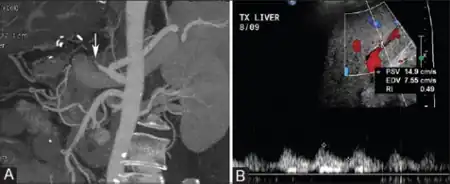

Hepatic artery thrombosis may cause severe elevations in serum aminotransferases, alanine transaminase (ALT) and aspartate transaminase (AST).[4] Often the AST is greater than the ALT.[4] Hepatic artery thrombosis is usually diagnosed with ultrasound with doppler, although it may be diagnosed using computed tomography (CT) or magnetic resonance imaging (MRI).

Hepatic artery thrombosis is diagnosed with ultrasound with doppler, which shows a lack of blood flow through the hepatic artery.[2] Hepatic artery thrombosis may also be diagnosed using CT or MR imaging, which would show evidence of a blood clot within the hepatic artery.[2]